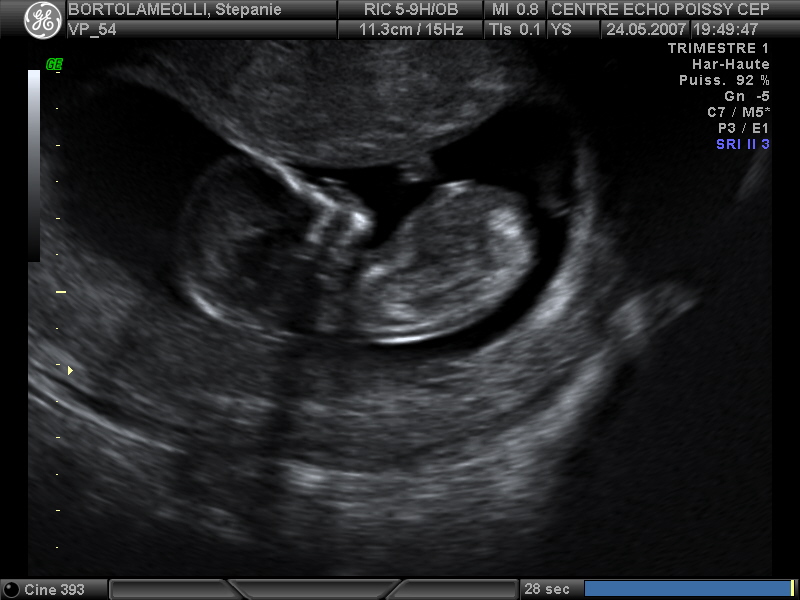

Echographies

Mai 2007